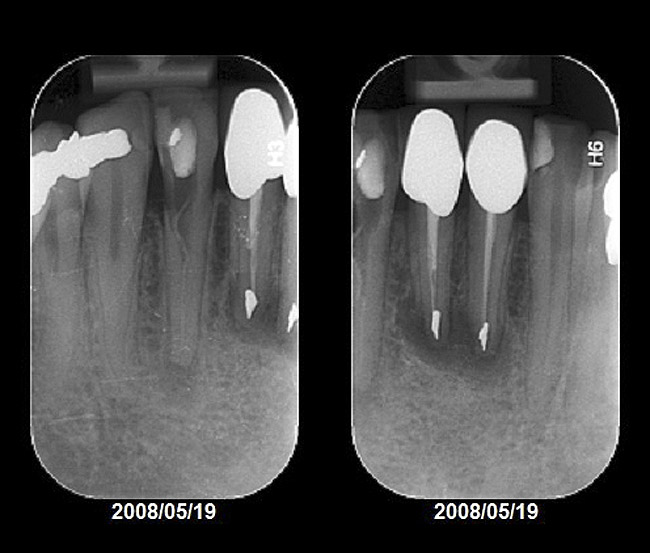

Radiographic evidence of external root resorption on tooth No. 26 and periapical radiolucencies with a history of prior endodontic treatment, including apicoectomies, were present on the mandibular central incisors (Figure 2).

Figure 2  Initial periapical radiographs showing failed endodontic treatment of Nos. 24 and 25, and root resorption, No. 26.

Figure 2